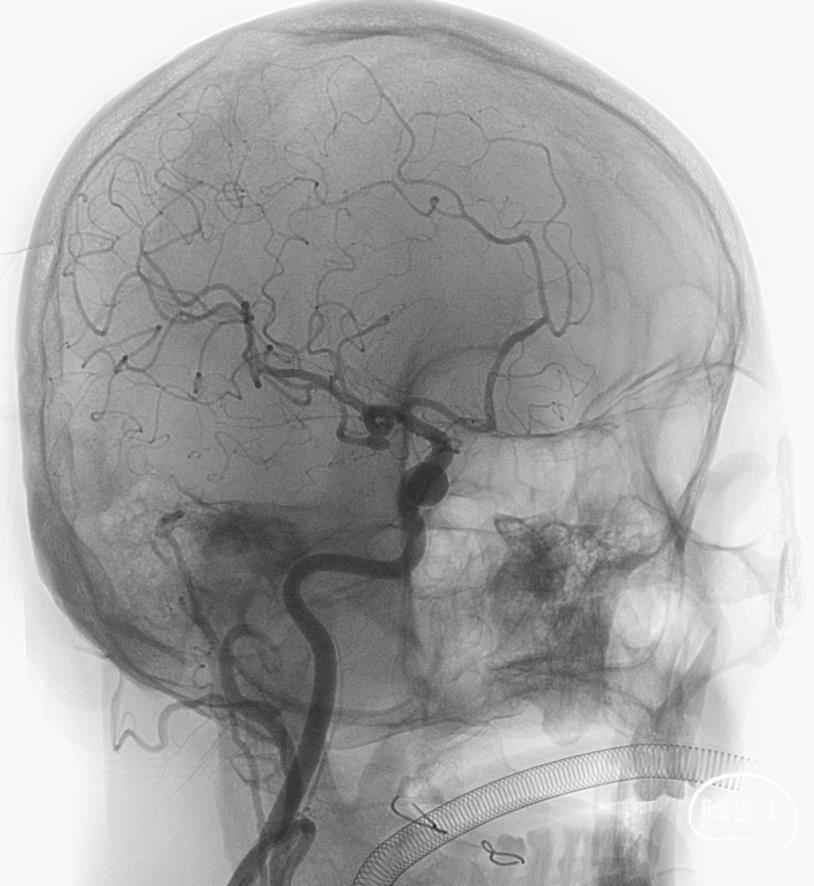

结束前造影。

患者全麻复苏后出室,无神经功能缺损。一切顺利。

本例采用的Y型支架,是第三个技术难点。Atlas开环支架,可以对动脉瘤颈起到较好的保护。但本例动脉瘤与M1分叉后的两大主要分支关系均密切,有可能单侧置入支架的效果仍不满意。考虑到有可能行Y型支架置入,在方案设计时,释放完第1枚支架,便在腔内通过穿网眼技术,将SL-10导管输送至另一分支。这样实际上是在支架和微导管辅助下进行动脉瘤栓塞。由于既往文献和实践中均有弹簧圈脱出甚至移位的报道,加之本例的特殊性,如果撤除SL-10导管,有可能造成此类后果。因此,我们在撤除栓塞微导管后仔细观察,结果发现终末弹簧圈稍有脱出。随即采用Crossing-Y技术释放支架,加强对瘤颈和载瘤血管的保护。动脉瘤栓塞效果满意,瘤颈和载瘤动脉保护良好。